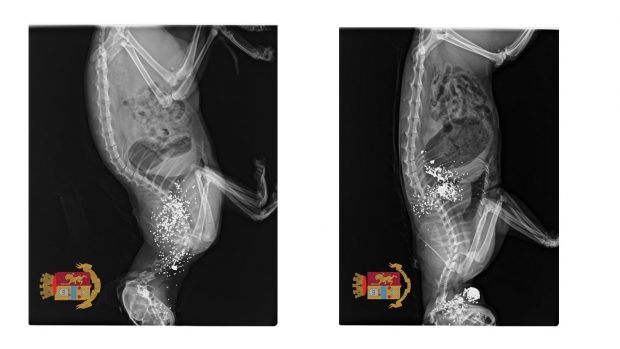

Secondo quanto emerso dalle investigazioni dei poliziotti l’uomo, titolare di porto di fucile per uso caccia, dopo aver ucciso a colpi di fucile caricato a pallini due gatti randagi che si aggiravano nei pressi della sua abitazione, si sbarazzava delle carcasse chiudendole all’interno di un sacco di plastica e gettando il tutto nell’immondizia.